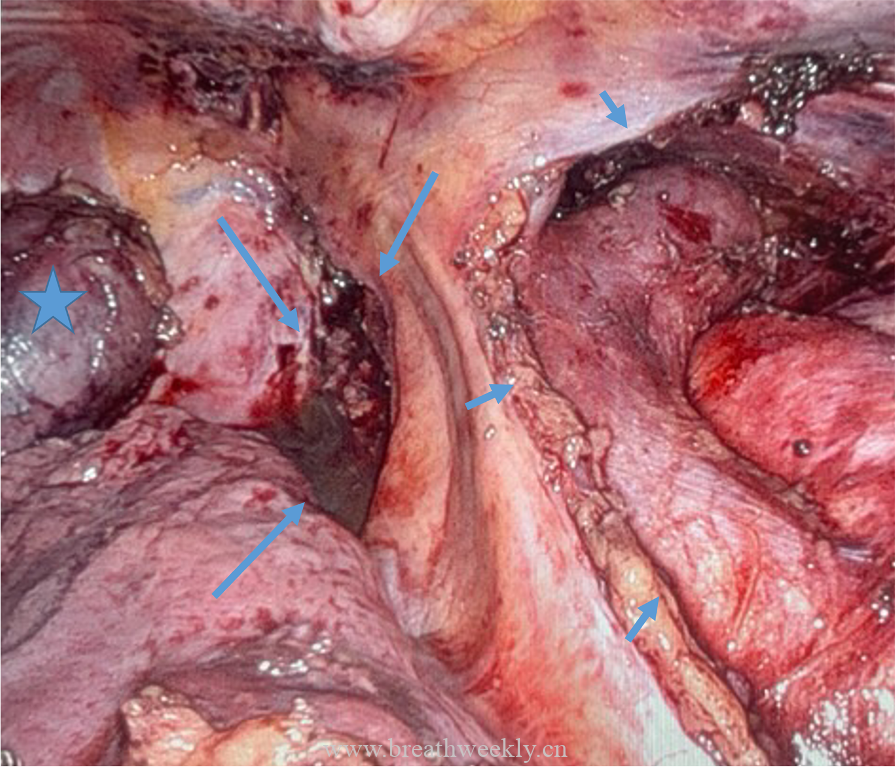

临床过程:因纵隔病灶位置位于甲状腺右叶后下方,术前考虑异位胸腺瘤或异位甲状旁腺腺瘤。CT及超声示无claw sign,排除甲状腺来源。99mTc-Sestamibi显像定位病灶。MG予糖皮质激素及IV免疫球蛋白治疗效果良好;高钙血症予IV补液及cinacalcet治疗。最终行机器人辅助纵隔甲状旁腺腺瘤及胸腺切除术,病理确诊甲状旁腺腺瘤。术后患者恢复良好。